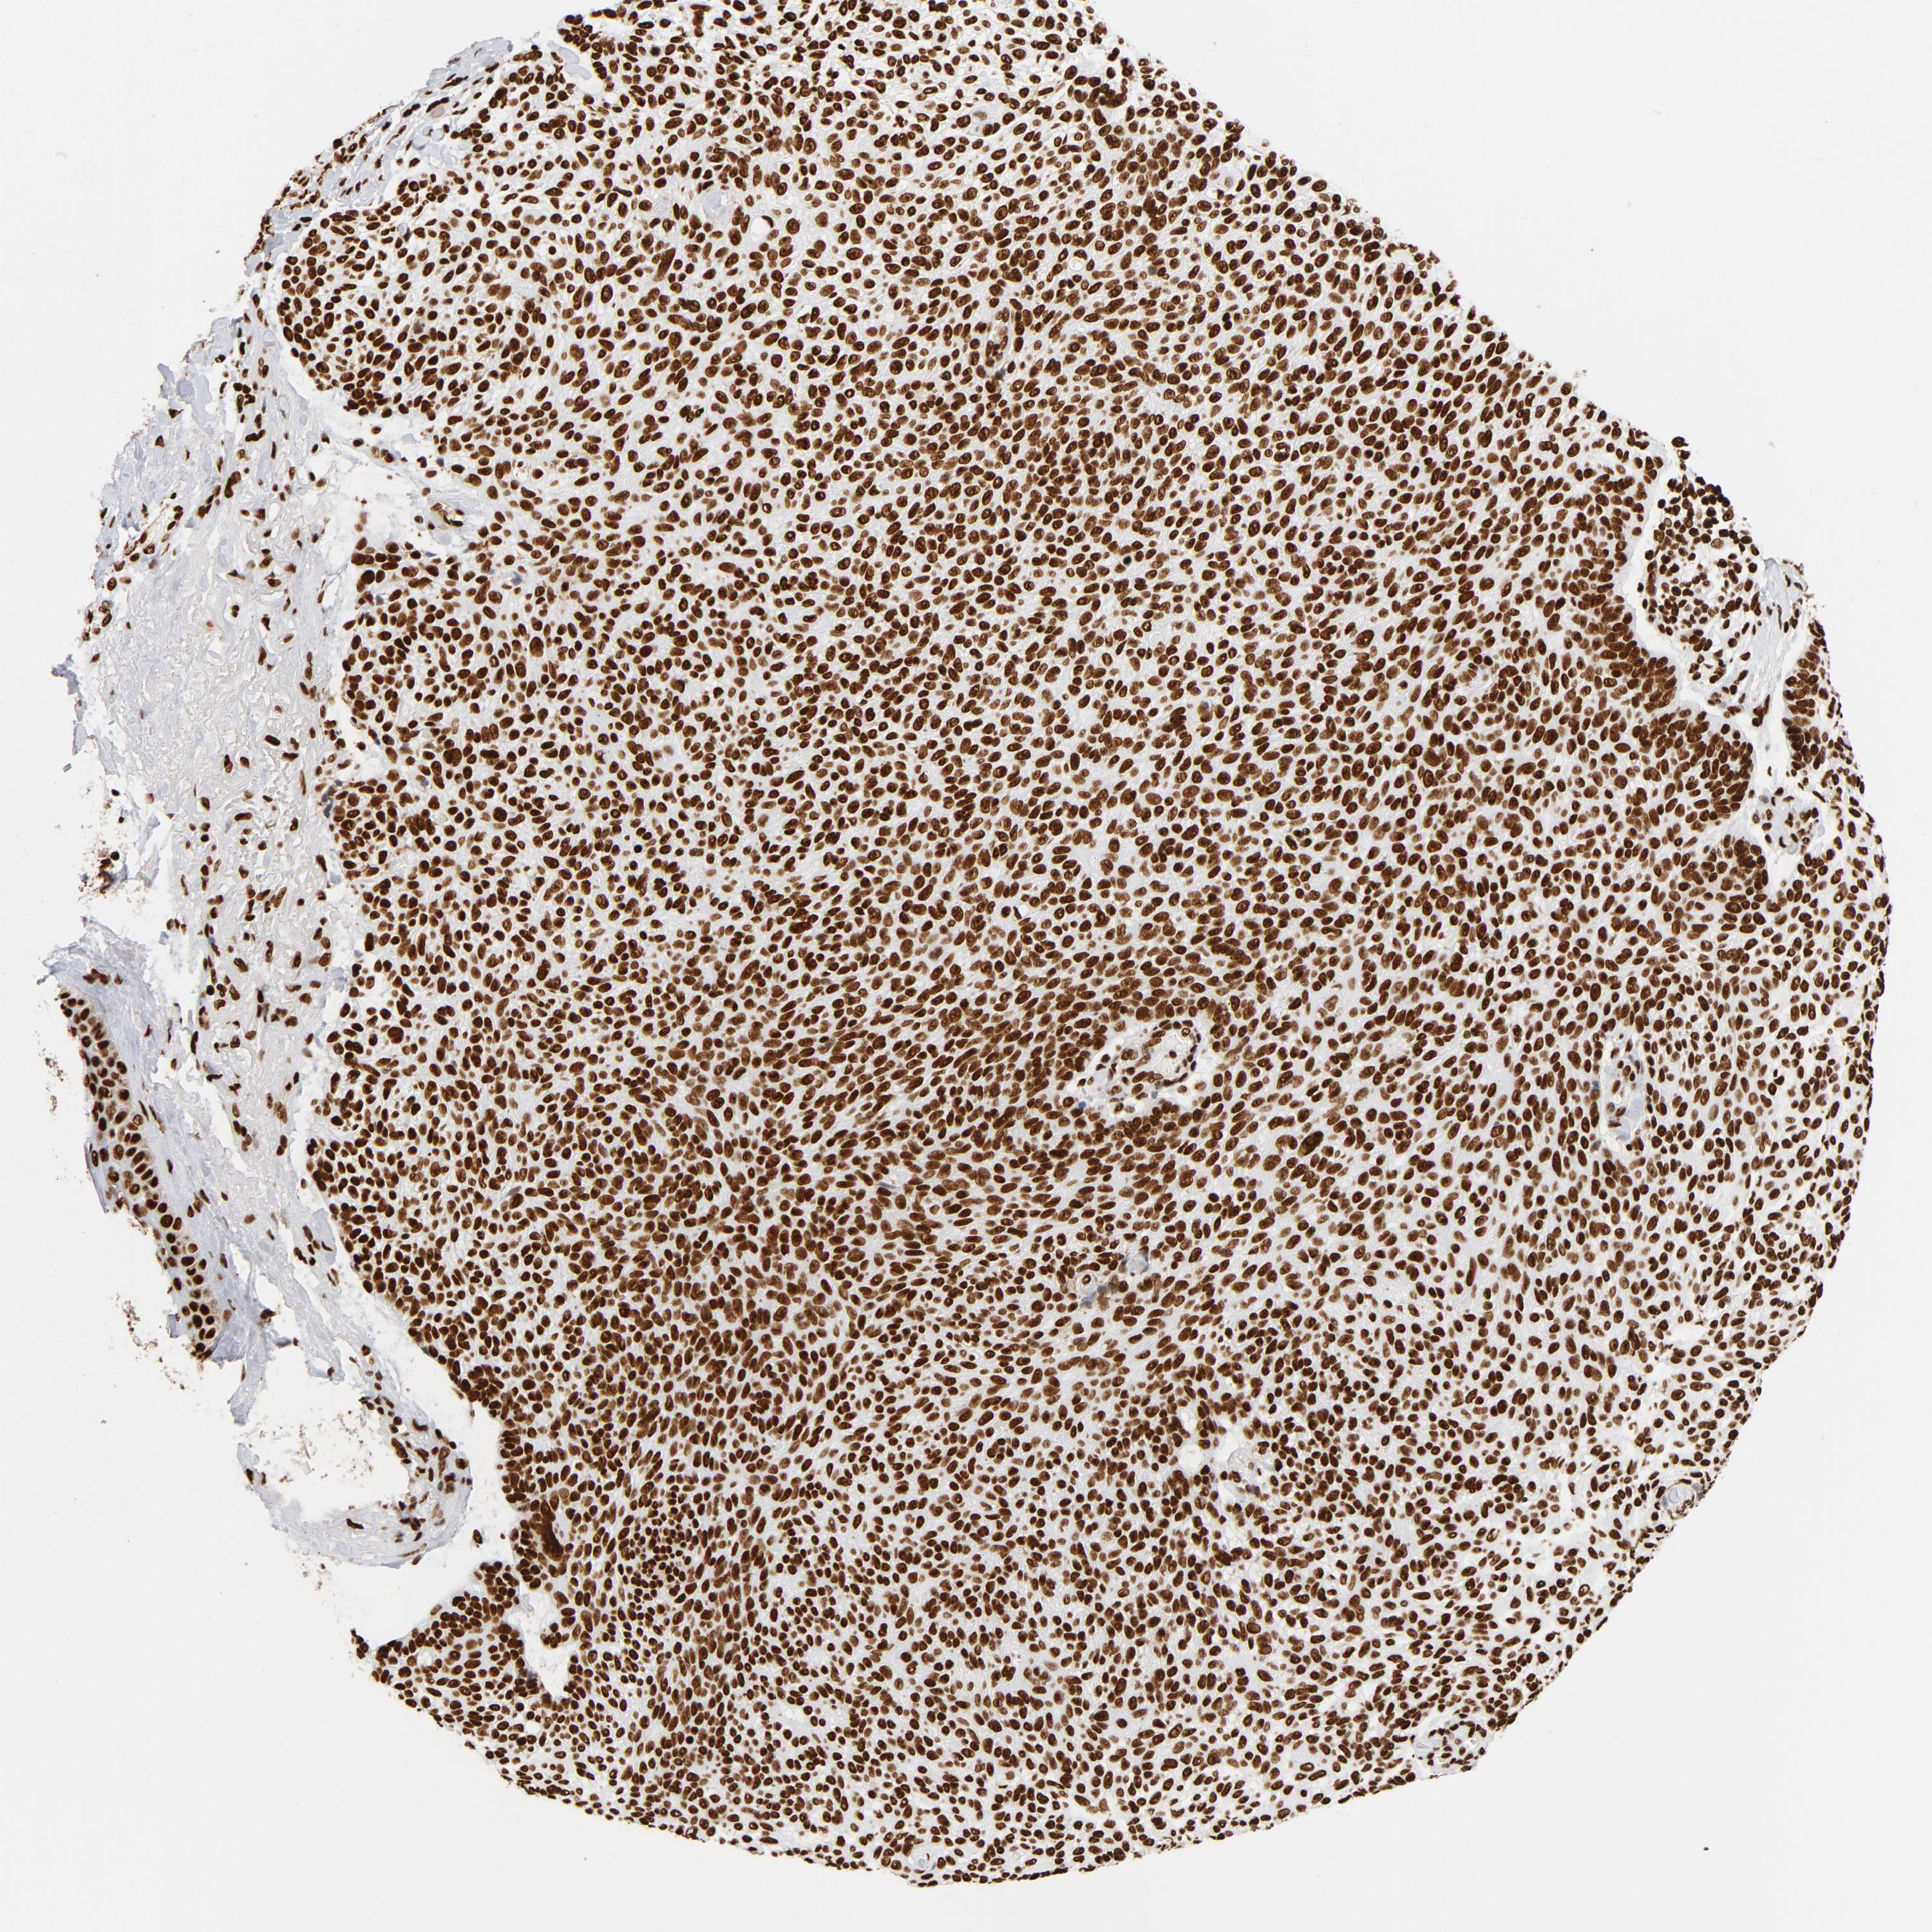

SKIN CANCER - Protein expressioni

A mouse-over function shows sample information and annotation data. Click on an image to view it in a full screen mode. Samples can be filtered based on level of antibody staining by selecting one or several of the following categories: high, medium, low and not detected. The assay and annotation is described here.

Antibody stainingi

Antibody staining in the annotated cell types in the current human tissue is reported as not detected, low, medium, or high, based on conventional immunohistochemistry profiling in selected tissues. This score is based on the combination of the staining intensity and fraction of stained cells.

Each image is clickable and will lead to virtual microscopy that enables deeper exploration of all samples and also displays staining intensity scores, fraction scores and subcellular localization as well as patient and tissue information for each sample.

Staining

High

Medium

Low

Not detected

Intensity

Strong

Moderate

Weak

Negative

Quantity

>75%

75%-25%

<25%

None

Location

Nuclear

Cytoplasmic/membranous

Cytoplasmic/membranous,nuclear

Squamous cell carcinoma, NOS

Squamous cell carcinoma, metastatic, NOS

Basal cell carcinoma